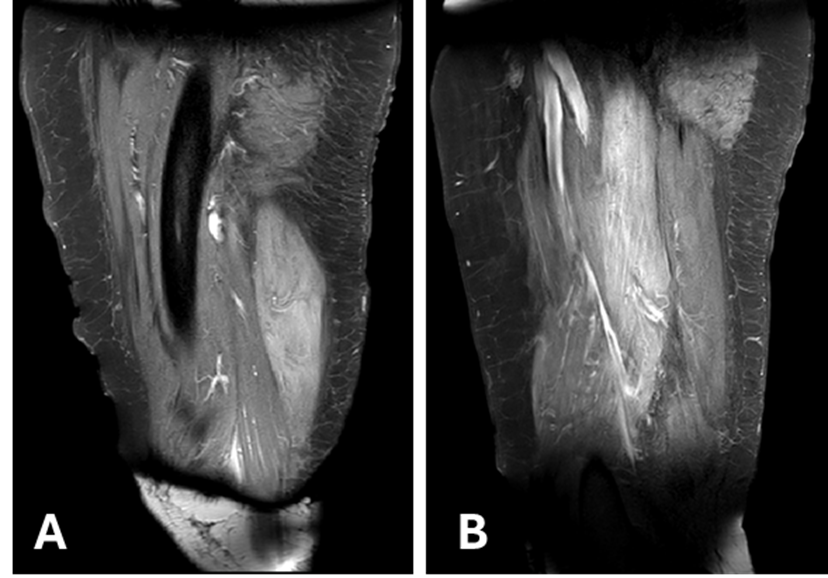

Lymphedema due to Podoconiosis in Brazil

José Maria Pereira de Godoy, Henrique José Pereira de Godoy, Lívia Maria Pereira de Godoy

bjcr36